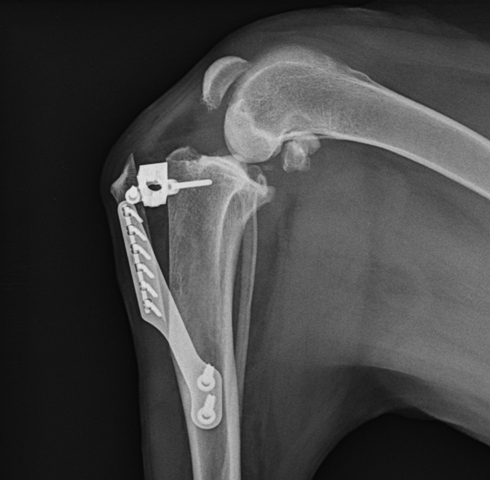

TTA

Ortopedija